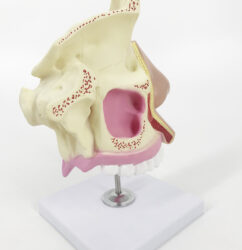

ATL-114 ADVANCED EAR INPECTION SIMULATOR SOFT

ATL-115 ADVANCED EAR IRRIGATION SIMULATOR SOFT

ATL-116 ADVANCED EAR DIAGONOSTIC SIMULATOR SOFT